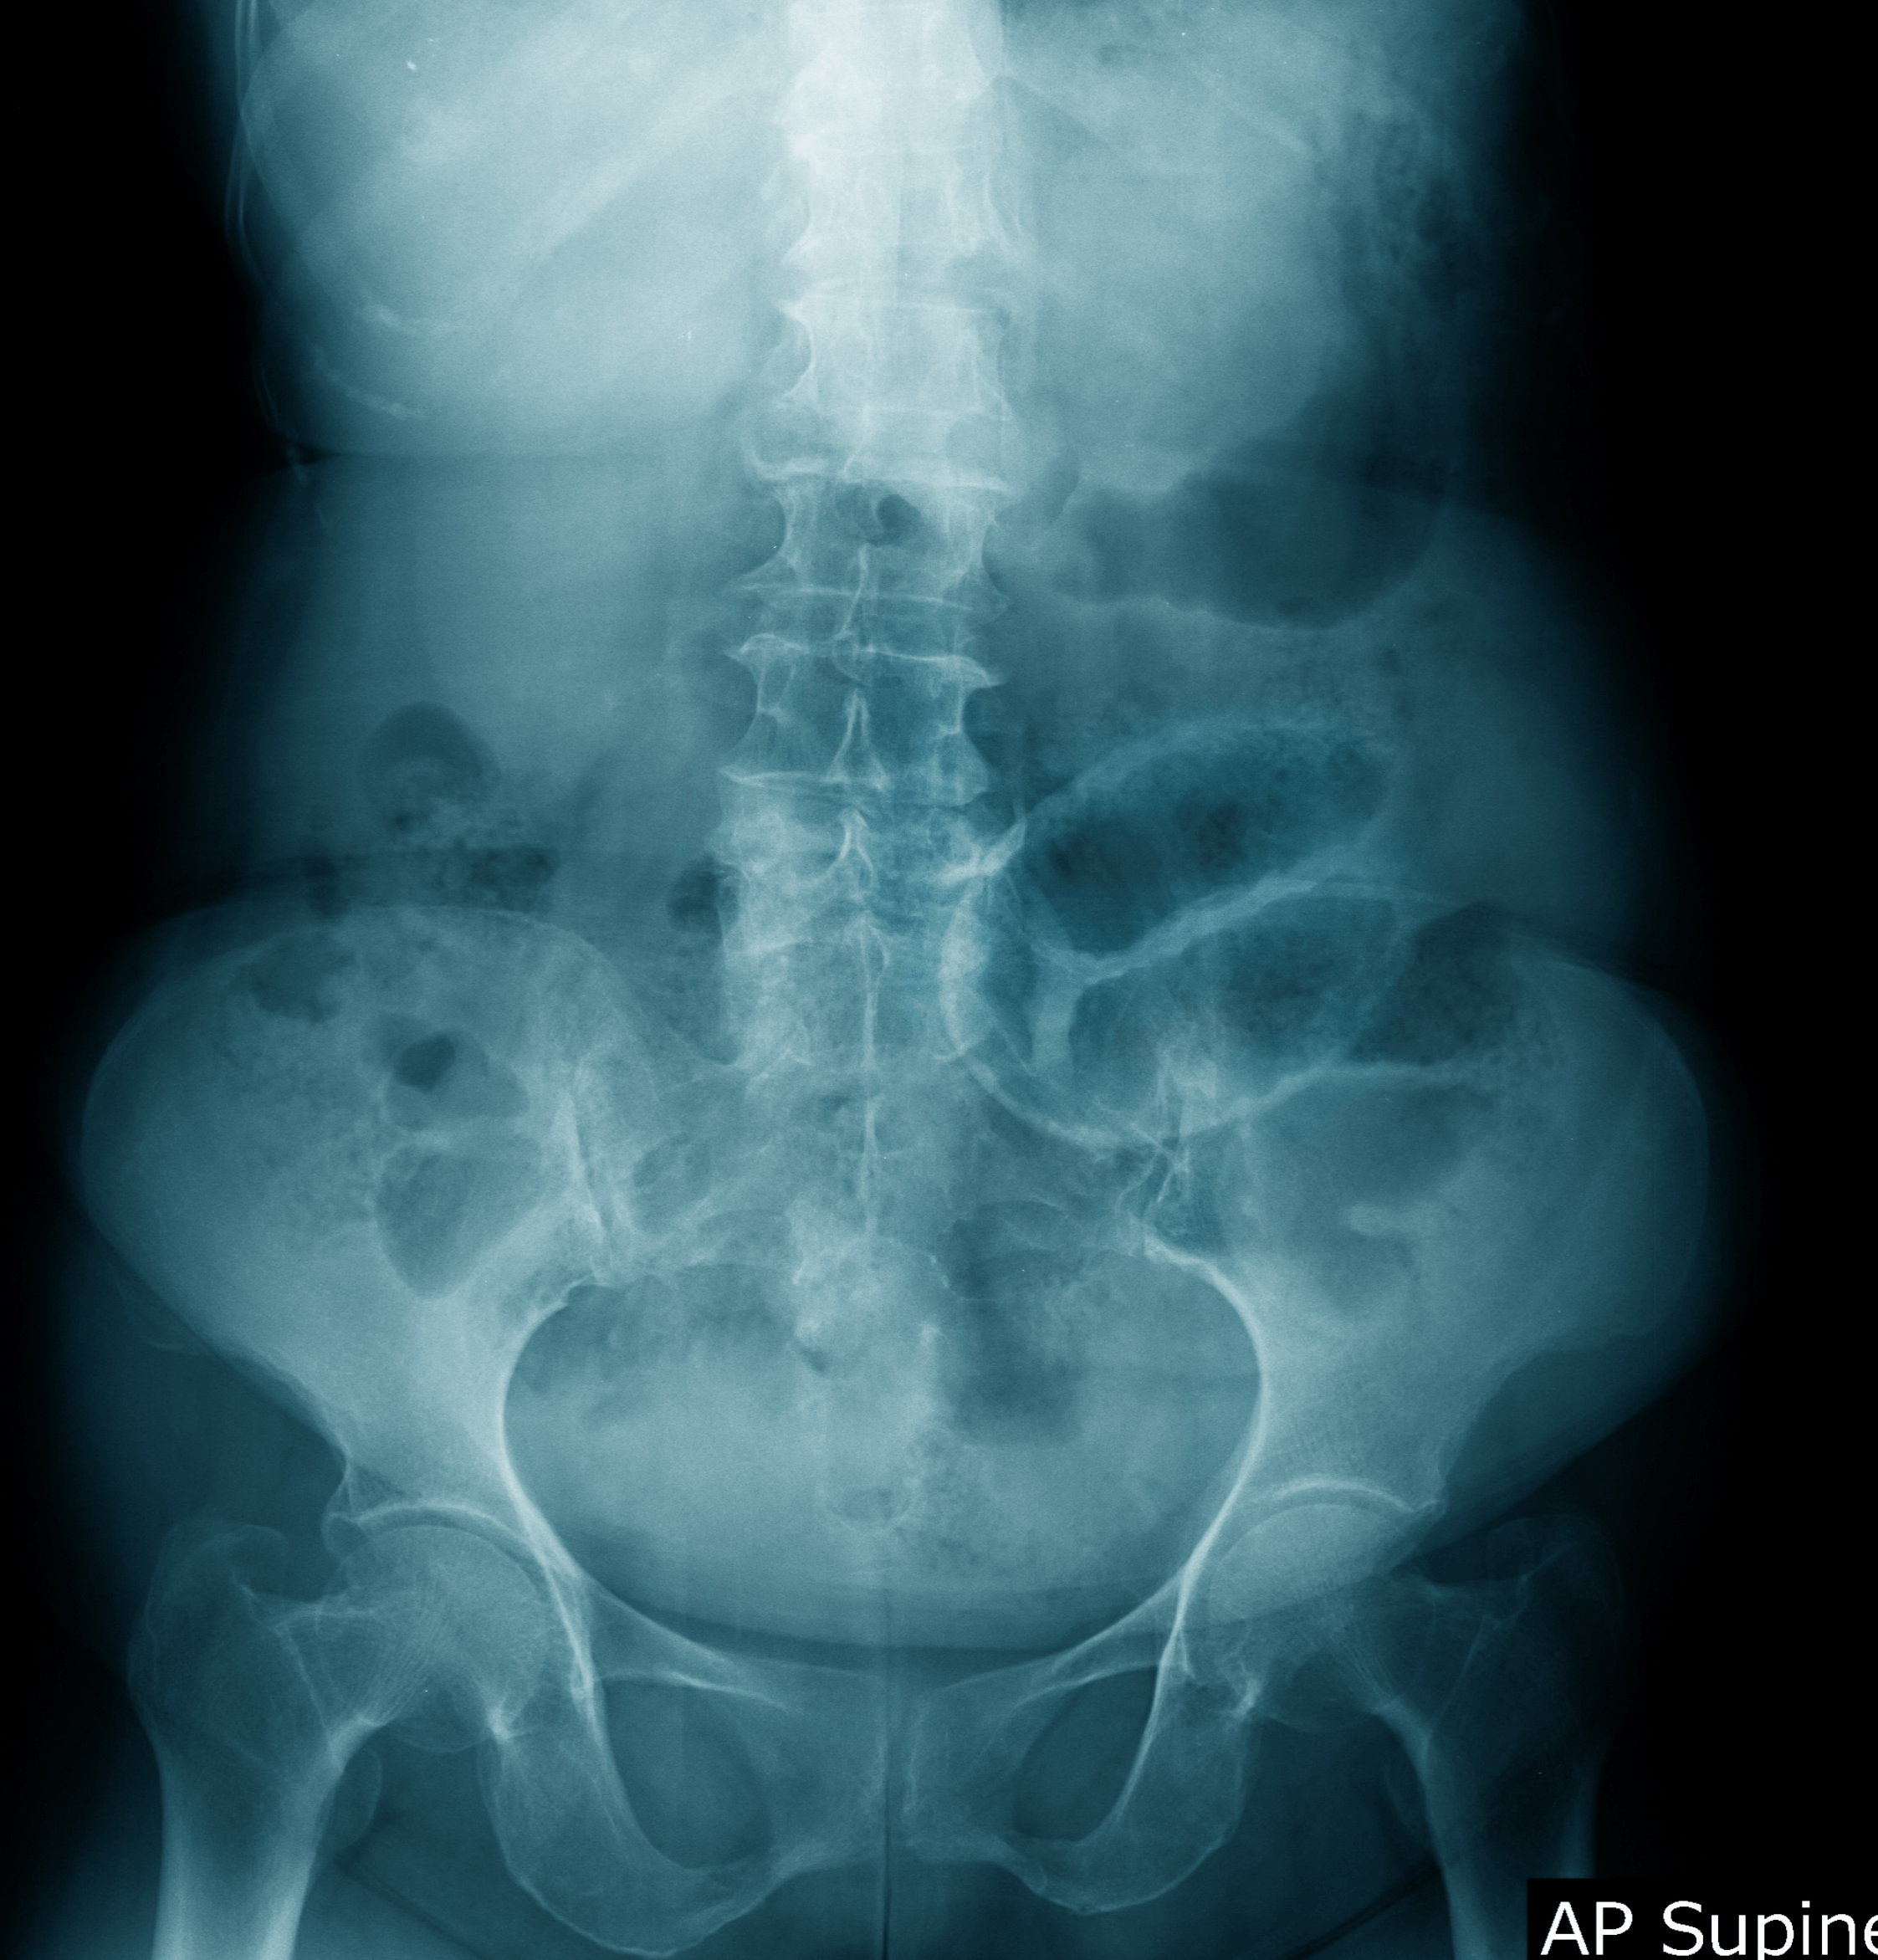

Radiografia addome

Che cos'è la radiografia all'addome?

La radiografia dell’addome, o RX addome, è un esame diagnostico che utilizza i raggi X per creare immagini dettagliate delle strutture interne dell'addome. Questo esame permette di visualizzare le ossa, che appaiono molto più chiare rispetto agli altri tessuti, e gli organi, che risultano più scuri.

L'esame radiografico diretto dell'addome viene condotto utilizzando un fascio di raggi X che attraversa il corpo e si imprime su una pellicola, creando un'immagine fotografica delle strutture interne. L'addome viene scansionato con un’apparecchiatura radiografica portatile, che può essere utilizzata sia in posizione distesa su un lettino che in piedi.

La radiografia dell’addome è utilizzata principalmente per individuare calcoli renali o alla colecisti, corpi estranei ingeriti, e sospette occlusioni o perforazioni intestinali. È un esame di primo livello di urgenza, spesso utilizzato come monitoraggio o preliminare ad altri esami più approfonditi, come la risonanza magnetica o la TAC.

La radiografia permette di vedere chiaramente le ossa, che appaiono bianche e compatte, mentre gli organi e i tessuti molli risultano più scuri. Questo contrasto aiuta a identificare anomalie come calcoli, corpi estranei, e segni di occlusioni o perforazioni intestinali.